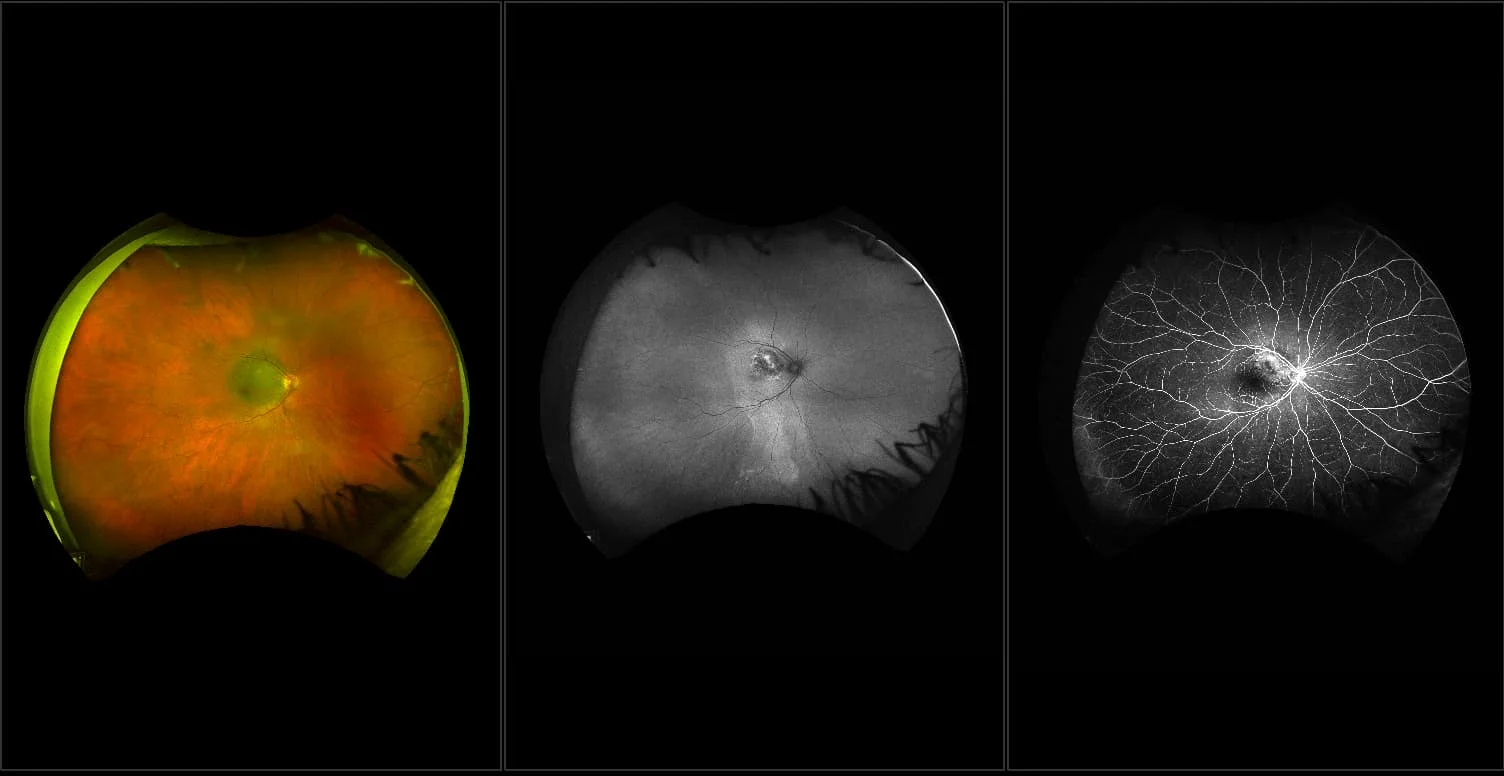

Silverstone - Dry AMD with ERM, RG, OCT

Age-related macular degeneration is found in two forms 1. Dry early form. 2. Wet (serous leakage or whole blood). Early dry form typically has drusen (usually around 63u) and RPE degeneration and only needs periodic follow-ups, intermediate dry form has large drusen (>125u) and RPE degeneration and proliferation which requires examinations every 3 to 6 months depending on the severity of the presentation.